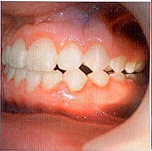

В течение 5-ти месяцев использования межчелюстной тяги динамика коррекции окклюзии по сагиттали слабоположительная. Кооперация с пациентом и его родителями ухудшилась, у мальчика значительно ухудшилась гигиена, межчелюстную тягу носил недостаточно, поэтому этап коррекции по сагиттали и вертикали оказался затруднен. Родители стали настаивать на снятии аппарата, т.к. положение передних зубов их устраивало, а смыкание в боковых отделах их не интересовало (рис. 4-6).

Рис. 4

Рис. 5

Рис. 6

В результате 12-месячного ортодонтического лечения нам удалось успешно провести лечение экструзиоинного вывиха верхних резцов. Верхние резцы заняли правильное положение относительно нижних, их перекрытие составило примерно 2,5-3 мм. Но сагиттальные взаимоотношения по-прежнему соответствуют III классу Энгля и сохранились бугровые окклюзионные взаимоотношения. На ОПТГ и прицельной рентгенограмме зубов 1.1.,2.1 и 2.2 периодонтальная щель сохранена на всей протяженности корней. Наблюдается небольшая апекальная резорбция верхушек корней 1.1,2.1 и 2.2 зубов.